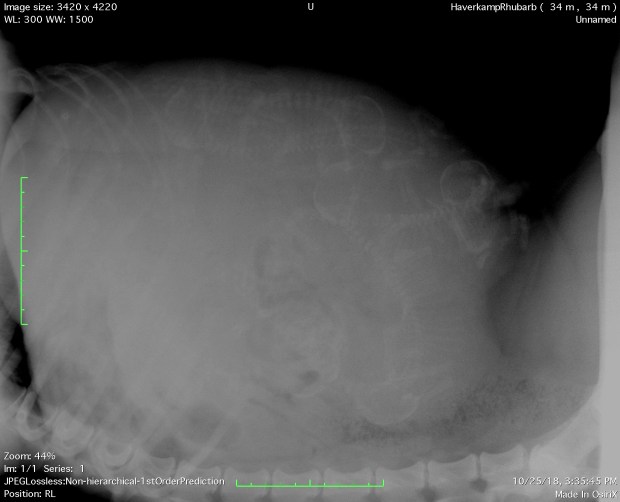

Well, Ruby had an x-ray today, and it appears as though seven puppies are growing in there. All appear healthy at this point, although one does look to be on the small side. We cannot predict an exact birthdate, but probably early November.

Seven baby puppies are growing quickly in Ruby’s belly! October 25th, 2018